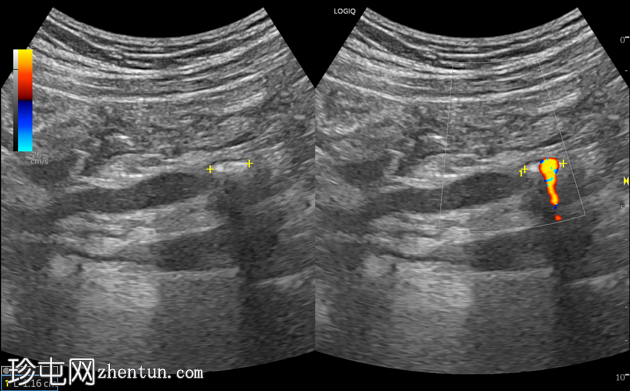

右侧中段输尿管结石,大小约1厘米,呈高回声,伴有声影,并可见闪烁伪影,导致中度右侧肾积水。

闪烁伪影(TA)是一种重要的彩色多普勒现象,对

泌尿

系结石的超声诊断至关重要。它表现为在强反射性高回声结构(结石)后方产生的离散、快速且交替的红蓝信号混合。

这种伪影显著提高了超声的敏感性,尤其适用于小型、无声影的结石或被周围组织遮挡的结石。